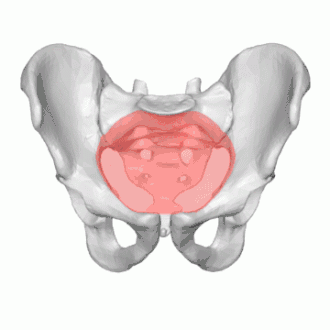

The pelvic inlet (shown in red)

The pelvic inlet or superior aperture of the pelvis is a planar surface which defines the boundary between the pelvic cavity and the abdominal cavity (or, according to some authors, between two parts of the pelvic cavity, called lesser pelvis and greater pelvis). It is a major target of measurements of pelvimetry.

Its position and orientation relative to the skeleton of the pelvis is anatomically defined by its edge, the pelvic brim. The pelvic brim is an approximately apple-shaped line passing through the prominence of the sacrum, the arcuate and pectineal lines, and the upper margin of the pubic symphysis.

The edge of the pelvic inlet (pelvic brim) is formed as follows:

Anteriorly

by the pubic crest (or pubic symphysis)

Laterally

by the iliopectineal line

Posteriorly

by the anterior margin of the base of the sacrum (or the ala of sacrum) and sacrovertebral angle (or sacral promontory)